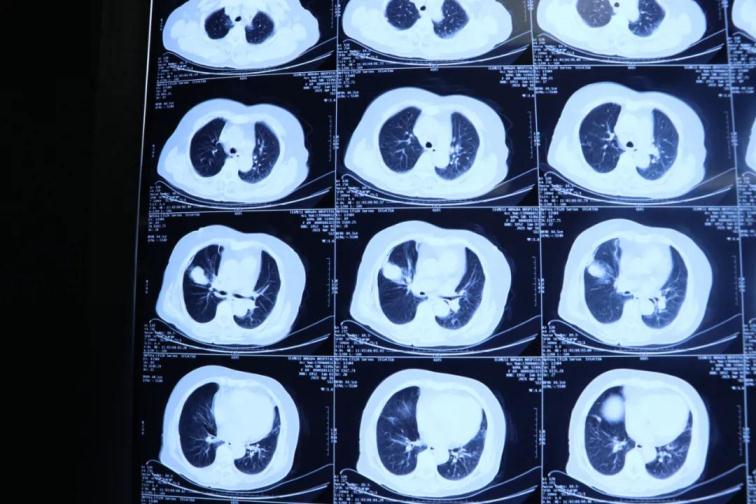

周鋼主任帶領(lǐng)胸外科團(tuán)隊(duì)經(jīng)過(guò)認(rèn)真分析病人病情,查閱大量國(guó)內(nèi)外最新資料,看到國(guó)際上目前采取射頻消融,激光消融還有氬氦刀等先進(jìn)微創(chuàng)技術(shù)治療惡性腫瘤,國(guó)內(nèi)同類手術(shù)技術(shù)也是剛剛起步,同時(shí),基于科室醫(yī)療團(tuán)隊(duì)在肺小結(jié)節(jié)CT定位技術(shù)穿刺病理上的先期業(yè)務(wù)培訓(xùn)和良好基礎(chǔ),決定采取目前國(guó)際上一流氬氦刀微創(chuàng)手術(shù)技術(shù)治療這位患者的肺部腫瘤。

為了提高CT影像下肺腫瘤定位的精準(zhǔn)度,術(shù)前胸外科團(tuán)隊(duì)聯(lián)合CT影像科趙文禮主任和董明鑫醫(yī)師詳細(xì)研究了肺CT定位方案,采取國(guó)際上先進(jìn)的CT網(wǎng)格定位法,對(duì)肺腫瘤精確定位,定位精度可達(dá)5mm以內(nèi)。經(jīng)過(guò)團(tuán)隊(duì)合作充分準(zhǔn)備后對(duì)肺癌實(shí)施了氬氦刀穿刺治療,微創(chuàng)穿刺針孔3mm,局麻鎮(zhèn)痛,分段治療40分鐘。病人全程在韋文康護(hù)士長(zhǎng)護(hù)理團(tuán)隊(duì)心肺監(jiān)測(cè)下進(jìn)行,確保了手術(shù)安全。

氬氦刀治療后即刻CT評(píng)價(jià)肺腫瘤核心密度下降,手術(shù)后5天CT評(píng)價(jià)肺癌與周圍正常肺組織對(duì)比,水腫帶形成,癌組織出現(xiàn)壞死。治療取得了良好效果。遠(yuǎn)期效果需要繼續(xù)隨訪觀察。病人手術(shù)后1周無(wú)并發(fā)癥痊愈出院。